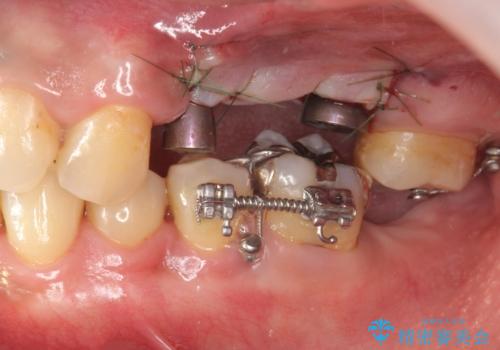

・対合歯の欠損による歯の挺出→マイクロインプラントを用いた小矯正を行うことで咬合平面を是正

今回、左下6は頬側歯頚部に虫歯があり圧下を行ったことからクラウンにより補綴を行いました。